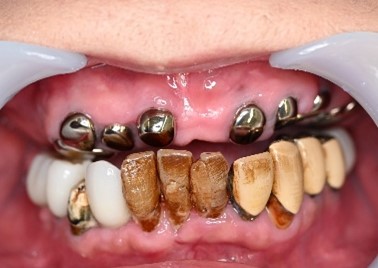

歯周病が進行し深刻な状態でした。保存することができない歯が上4本、下3本ありましたので、抜歯し、残った歯上4本、下7本の歯周病治療を徹底的にし、それらの歯を活用し上下マグネット式総入れ歯を入れました。

Before

赤丸は抜歯しました。上4本、下3本

After

【義歯を装着したところ】

【義歯を外したところ】